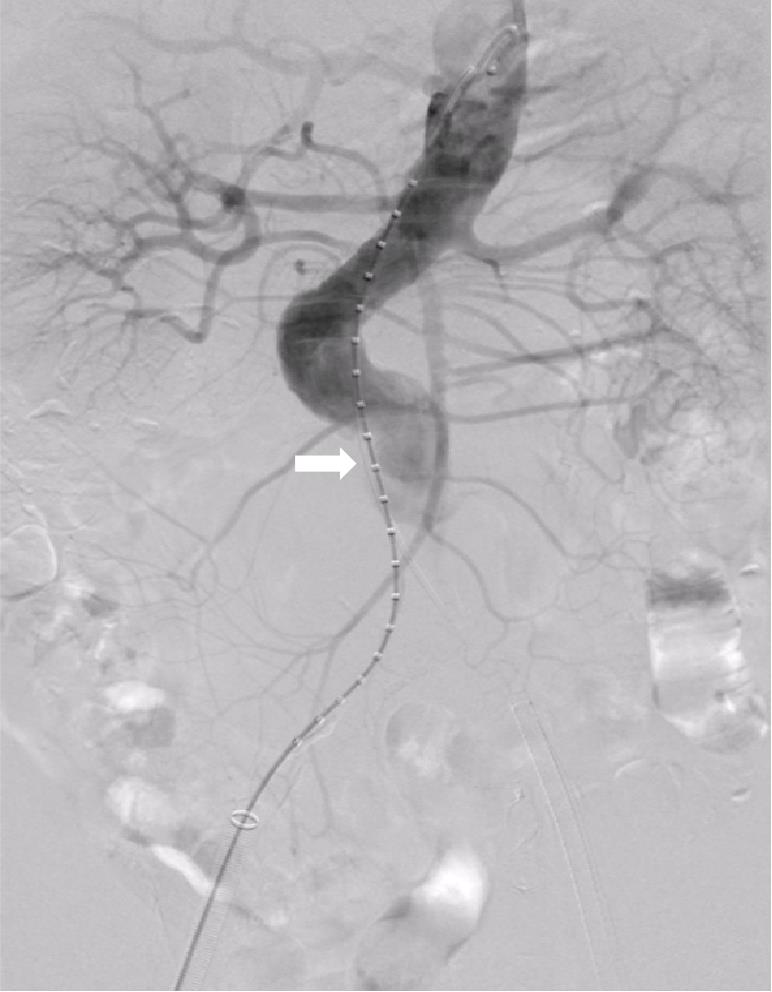

• Clinical application of three-dimensional visualization technology in assessing the spatial configuration of major hepatic vessels and liver lobar volume distribution

2026, 35(1):124-140. DOI: 10.7659/j.issn.1005-6947.250635

Abstract (93) HTML (137) PDF 3.82 M (171) Comment (0) Favorites

Abstract:Background and Aims The hepatic vascular and biliary systems exhibit substantial anatomical variability and complex spatial relationships, posing challenges for precise surgical planning based on conventional two-dimensional imaging. This study aimed to evaluate the clinical value of three-dimensional visualization in characterizing the spatial architecture of hepatic vasculature and bile ducts and to explore its association with hepatic volumetric distribution.Methods A total of 610 living liver donors and 158 patients with bile duct dilatation were retrospectively analyzed. Three-dimensional models of the hepatic artery, portal vein, hepatic veins, and bile ducts were reconstructed from contrast-enhanced CT images. Vascular and biliary anatomical patterns, spatial relationships, and their correlations with hepatic lobe and segmental volumes were systematically assessed.Results Three-dimensional visualization enabled intuitive and comprehensive depiction of hepatic vascular and biliary anatomy. Distinct portal vein configurations were associated with significant differences in regional liver volume distribution, with an increased proportion of the right posterior lobe observed in patients with specific portal vein branching patterns. The presence of an inferior right hepatic vein with a diameter ≥5 mm was also associated with a larger right posterior lobe volume. Analyses of extrahepatic and intrahepatic spatial relationships revealed relatively consistent positional patterns between the right hepatic artery, portal vein, and bile ducts, and a significant correlation was observed between the spatial courses of the right hepatic artery and the right posterior bile duct.Conclusion Three-dimensional visualization provides accurate preoperative assessment of hepatic vascular and biliary anatomy and clarifies complex spatial relationships and their volumetric implications. This technique offers critical anatomical support for precision hepatobiliary surgery and liver transplantation.